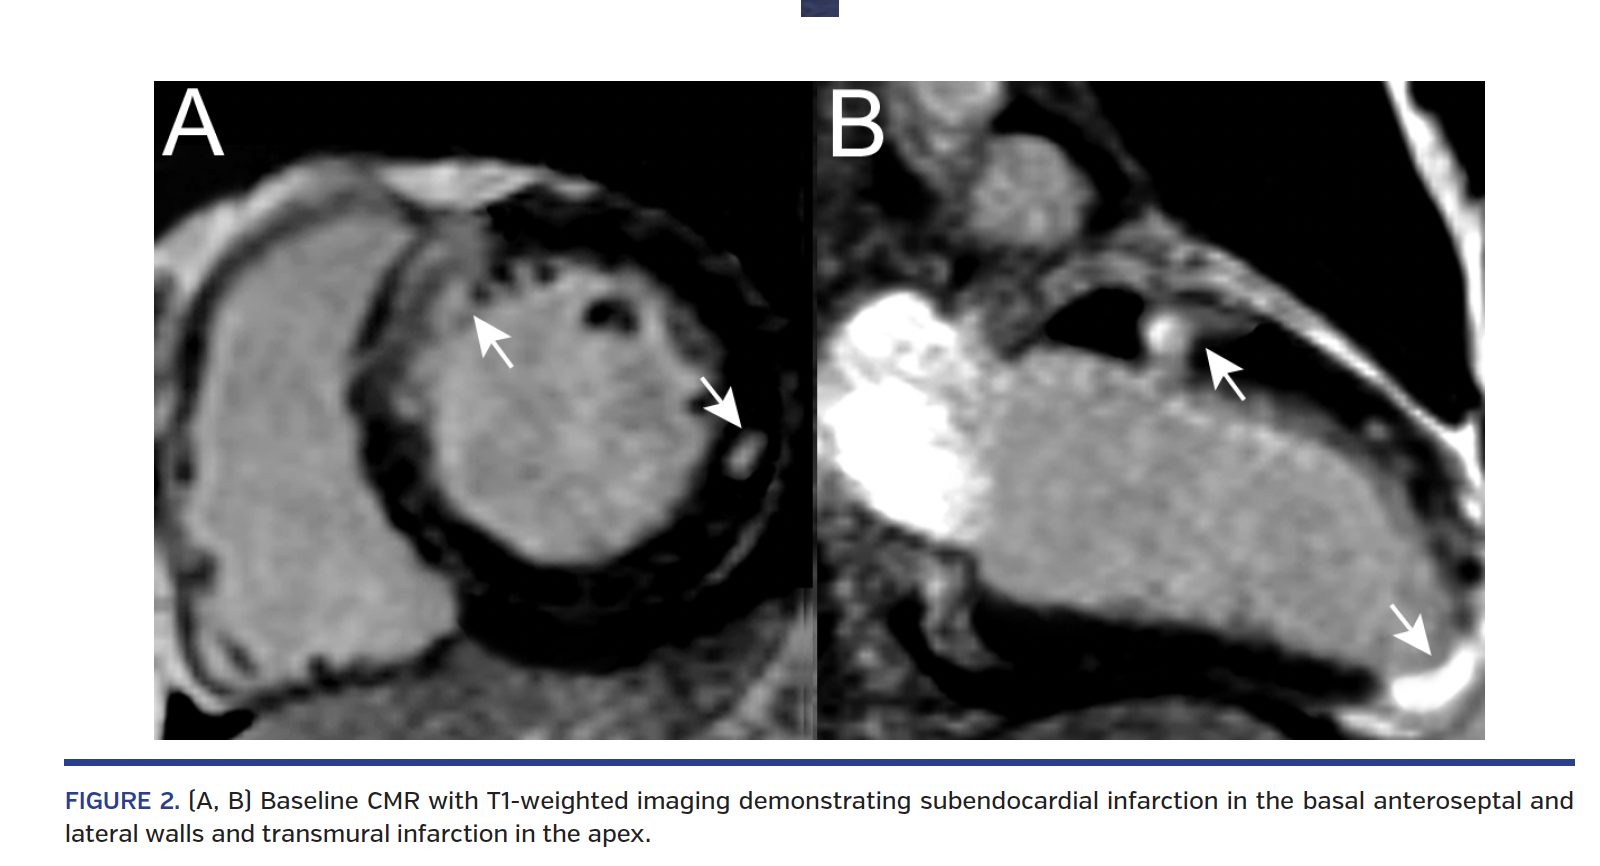

A 22-year-old, obese male smoker with untreated hyperlipidemia and family history of coronary artery disease presented with chest pain and ST-segment elevation in anterolateral leads at ECG following heavy marijuana and alcohol abuse. Coronary angiography showed a moderate stenosis in the proximal left anterior descending (LAD) coronary artery along with distal embolization (Figure 1A; Video 1). No concomitant coronary stenoses were noted, and TIMI 3 flow was present in the LAD. Optical coherence tomography (OCT) revealed plaque erosion with massive thrombi involving the distal left main coronary artery (LMCA) and ostial to mid LAD (Figure 1A; Video 2), along with preserved lumen area of the LAD. Given the diffuse extent of non-obstructive CAD involving the LMCA on OCT, aggressive medical thera-py with glycoprotein IIb/IIIa blocker, aspirin, ticagrelor, and high-dose statin was initiated. At discharge, cardiac magnetic resonance (CMR) imaging showed subendocardial infarction in the basal anteroseptal and lateral walls, and transmural infarction in the apex (Figure 2). After 3 months, repeat angiography with OCT demonstrated a non-obstructive lesion with fully healed fibroatheroma (Figure 1B; Videos 3 and 4). At 7 months, the patient was asymptomatic and control CMR showed preserved left ventricular function with resolution of myocardial edema (Figure 3; Video 5).